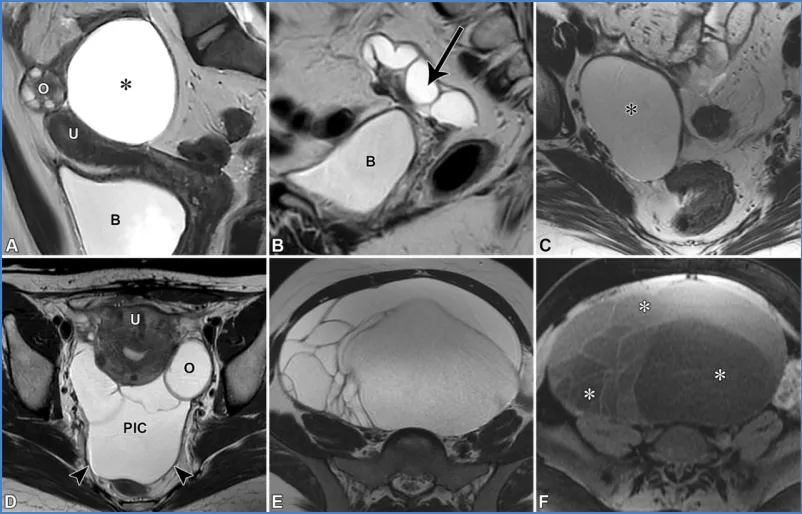

附件病变——对于卵巢来源的病变,鉴别诊断包括功能性囊肿、绝经后囊肿以及良性上皮性肿瘤,如浆液性或黏液性囊腺瘤(图23)。浆液性囊腺瘤通常为单房,偶尔为双侧,内充满单纯性液体,类似绝经后卵巢囊肿(36)。黏液性囊腺瘤为单侧、多房,由于黏液的存在,囊腔的T1和T2信号强度不定,形成“彩色玻璃”样表现(69)。双侧黏液性囊腺瘤样病变应警惕转移瘤的可能。

图23. 不同患者中无强化实性组织的各种妇科囊性病变的MRI图像。(A)矢状位T2加权图像显示一个卵巢旁囊肿,这是一个单房性单纯囊肿(*),位于子宫(U)和卵巢(O)附近但与之分离。B=膀胱。(B)矢状位T2加权图像显示一个输卵管积水,为扩张的、充满液体的管状结构(箭头),壁光滑且有输卵管内膜皱襞,与子宫和卵巢(未显示)分离。B=膀胱。(C)轴位T2加权图像显示一个浆液性囊腺瘤(*),这是一个长期存在的单房性囊肿。未能观察到与该病变分离的卵巢。(D)一位有过肠切除史的46岁女性患者的轴位T2加权图像显示一个腹膜包涵囊肿(PIC),这是一种多房性囊性病变,因粘连形成薄分隔,形态与腹膜腔一致(箭头),卵巢(O)悬浮于边缘。U=子宫。(E、F)轴位T2加权图像(E)和脂肪抑制T1加权图像(F)显示一个黏液性囊腺瘤,这是一个大型单侧多房性囊性肿块,囊腔信号强度不一(*;在F中最明显;*),类似彩色玻璃。

对于卵巢旁来源的病变,鉴别诊断包括卵巢旁囊肿、输卵管积水和腹膜包涵囊肿(图23)。卵巢旁囊肿是位于子宫和卵巢之间阔韧带内的圆形或椭圆形单房囊肿(70)。输卵管积水是卵巢附近呈C形或U形、充满液体的梗阻性输卵管,具有特征性的不完全隔膜或输卵管内膜皱襞。输卵管积水通常由盆腔炎性疾病引起的瘢痕导致,较少由子宫内膜异位症或手术引起(39)。腹膜包涵囊肿常见于有功能卵巢且既往有盆腔损伤(如手术、创伤、子宫内膜异位症)的绝经前女性,是符合腹膜腔形态并包绕卵巢的多房薄壁病变,呈现“网中蜘蛛”样表现(70)。